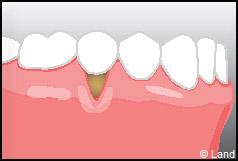

Outre la maladie parodontale, nous pouvons rencontrer des défauts de la gencive qui n’ont pas une origine infectieuse. Les plus fréquents de ces défauts sont les récessions gingivales, qui se traduisent par la migration de la gencive en direction de la racine (la racine est alors à nu).

Les conséquences de cette mise à nu de la racine dentaire sont multiples, le patient peut présenter une hypersensibilité dentaire et l’aspect de ces récessions peut être inesthétique. Dans ce cas, la chirurgie muco-gingivale est recommandée et elle peut se faire de différentes façons.

Les greffes de conjonctifs enfouis :

Destinées aux zones esthétiques, elles consistent à prélever la partie profonde du palais (site donneur).

Ce greffon est ensuite inséré sous la gencive au niveau de la récession (site receveur).